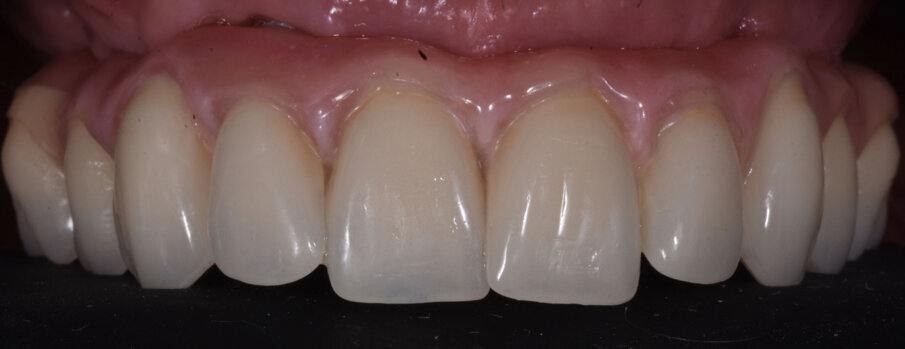

Il risultato finale evidenzia di aver raggiunto l’obbiettivo di ripristinare la funzione ma anche l’estetica in un paziente ancora giovane e motivato a mantenere il manufatto con una più accurata igiene orale (Figg. 9a, 9b). L’esame radiografico eseguito sei mesi dopo l’inserzione della protesi evidenzia la stabilità delle zone innestate precedentemente al posizionamento degli impianti e la precisione delle strutture protesiche (Fig. 10). In una visita di controllo ad un anno dall’inserzione della protesi si può notare il notevole miglioramento estetico prodotto dalla terapia implanto-protesica (Fig. 11).